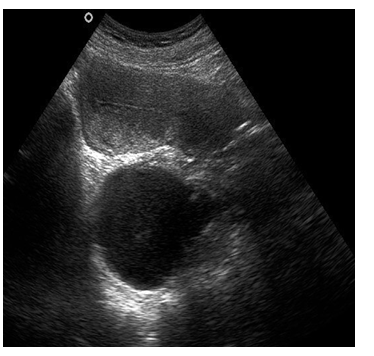

B超:左卵巢无回声6.2*6.3*5.5厘米,壁薄,透声好,无分隔。